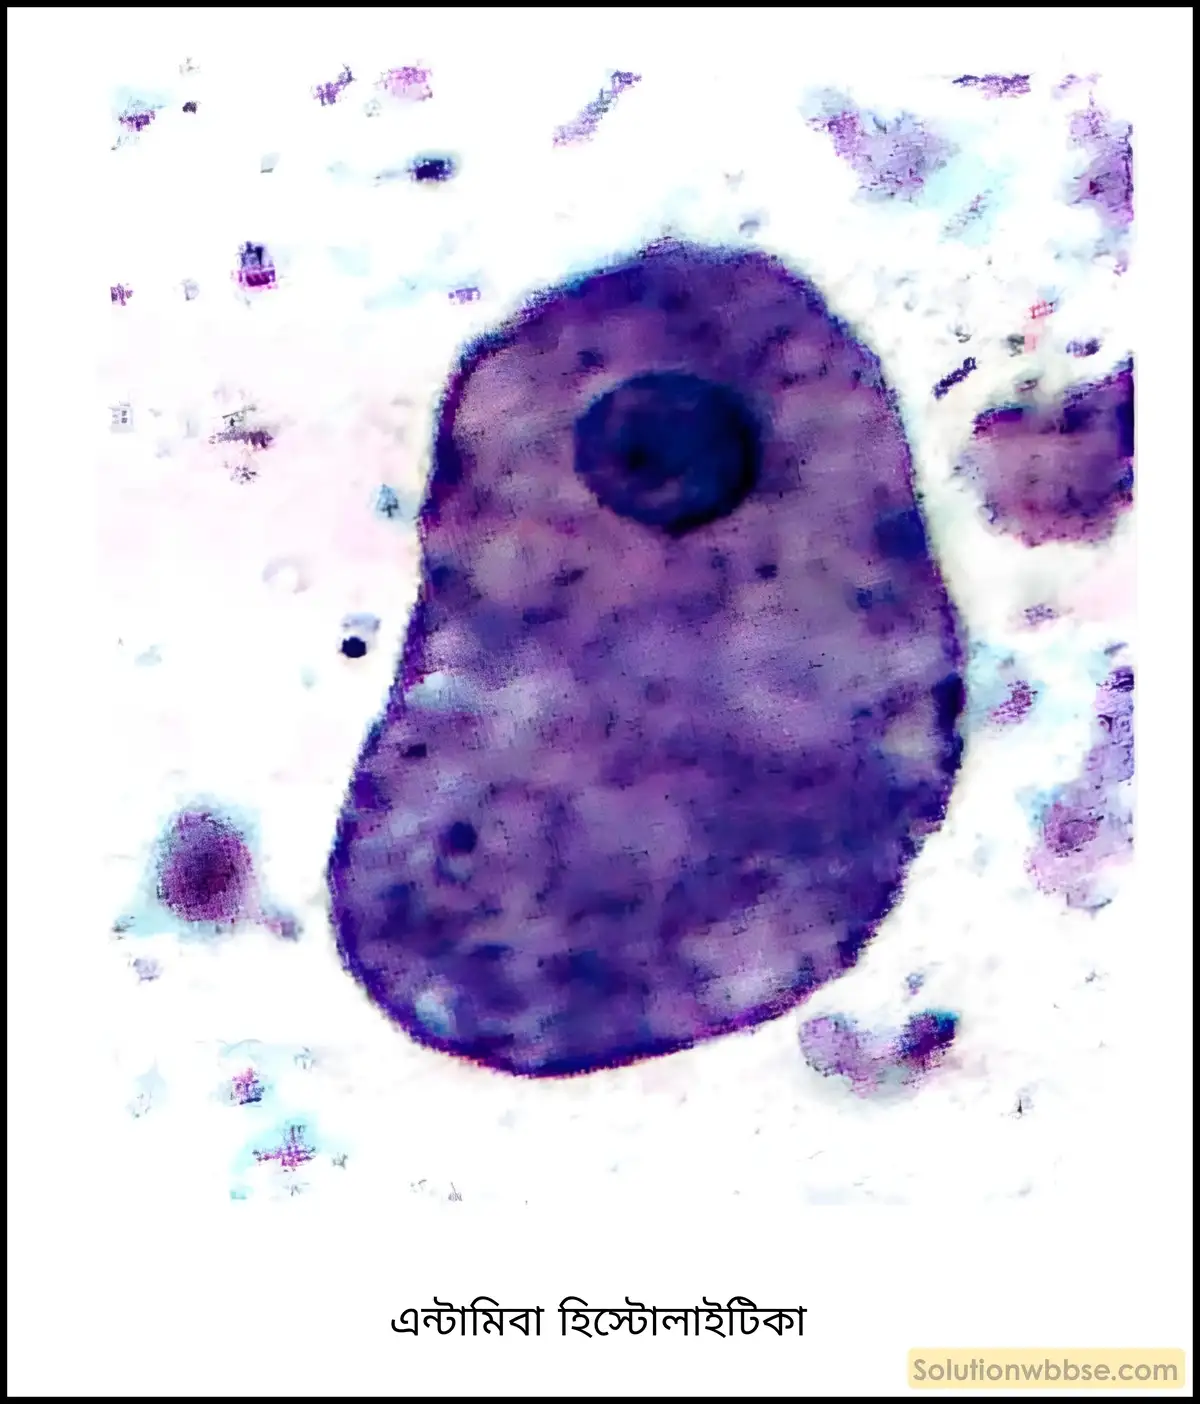

রোগের নাম – ডায়ারিয়া।

রোগের প্রকৃতি – এন্টামিবা হিস্টোলাইটিকা (Entamoeba histolytica) নামক পরজীবী বা আদ্যপ্রাণী ঘটিত রোগ।